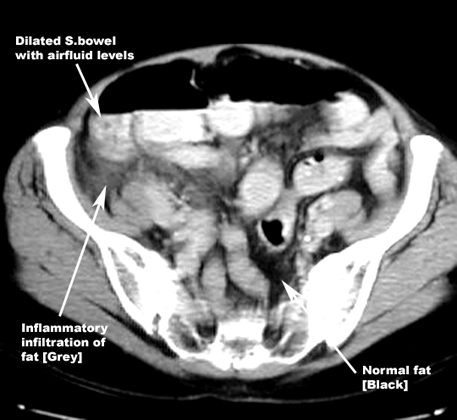

CT: Highly accurate

Signs: